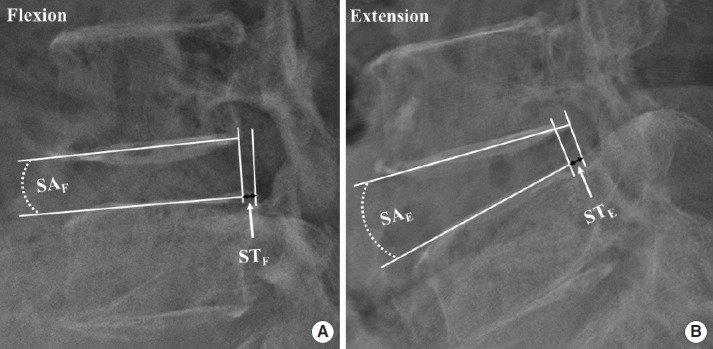

Methods: This retrospective study included 86 patients, divided into ULBD-UBE (n=34), STL (n=24), and MIS-TLIF (n=28) groups. We evaluated demographics and perioperative factors and assessed clinical outcomes using the visual analogue scale (VAS), Oswestry Disability Index (ODI), and neurogenic intermittent claudication (NIC). Radiological parameters assessed included lumbar lordosis, L4S1 Cobb angle (L4S1), T12S1 Cobb angle (T12S1), increased cross-sectional dural area (CSA), dynamic angulation (DA), dynamic slip (DS), and development of postoperative instability.

Results: The ULBD-UBE group showed a significantly shorter hospital stay duration and operation time and reduced blood loss than the other groups (p<0.001). ULBD-UBE group showed a trend towards greater VAS and ODI improvement at 1 month and postoperative NIC symptom relief. Radiologically, MIS-TLIF group exhibited lower postoperative DA and DS (p<0.001), indicating higher postoperative stability. Postoperative instability was lower in the ULBD-UBE group (2.9%) than in the STL group (16.7%) and similar to the MIS-TLIF group (0.0%) (p=0.028). The CSA was highest in the MIS-TLIF group (295.5%) compared to that in the other groups (ULBD-UBE, 216.3%; STL, 245.2%) (p<0.001).